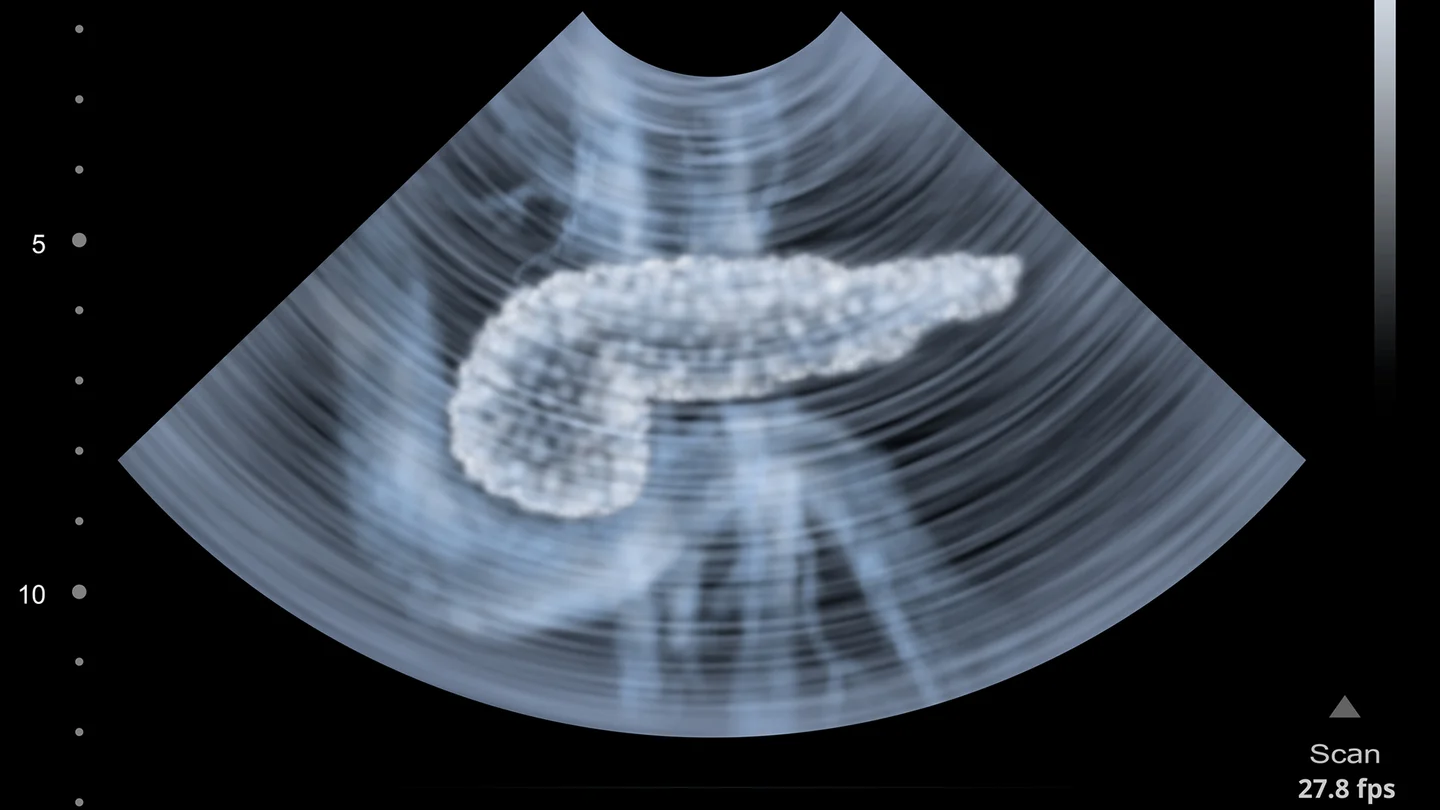

Bauchspeicheldrüsenkrebs: Ein Ultraschallbild, auf dem ein menschlicher Pankreas abgebildet ist. Bauchspeicheldrüsenkrebs: Ein Ultraschallbild, auf dem ein menschlicher Pankreas abgebildet ist.

ما سرطان البنكرياس؟

يشير الأطباء عادةً إلى الأورام التي تنشأ من الخلايا الغدية في قنوات البنكرياس، بمصطلح سرطان البنكرياس أو أورام البنكرياس الخبيثة. حيث إنها توجه العصارة الهضمية مما يسمى بالجزء الخارجي من البنكرياس نحو الأمعاء. وعندئذٍ يُشير المتخصصون إلى سرطان غدي في غدة خارجية الإفراز.